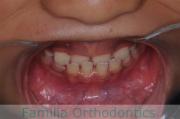

上の前歯の並びが気になるのできれいにしたい、ということで来院されました。マウスピース型矯正装置のひとつ、インビザライン/InvisalignR(薬機法および医薬品副作用被害救済制度の対象外)を用いて治療しました。

非抜歯で2年弱、20回程度の通院で治療が完了しました。

マウスピース矯正は、患者さんの協力に治療結果が左右されるところはリスクと言えるかもしれません。